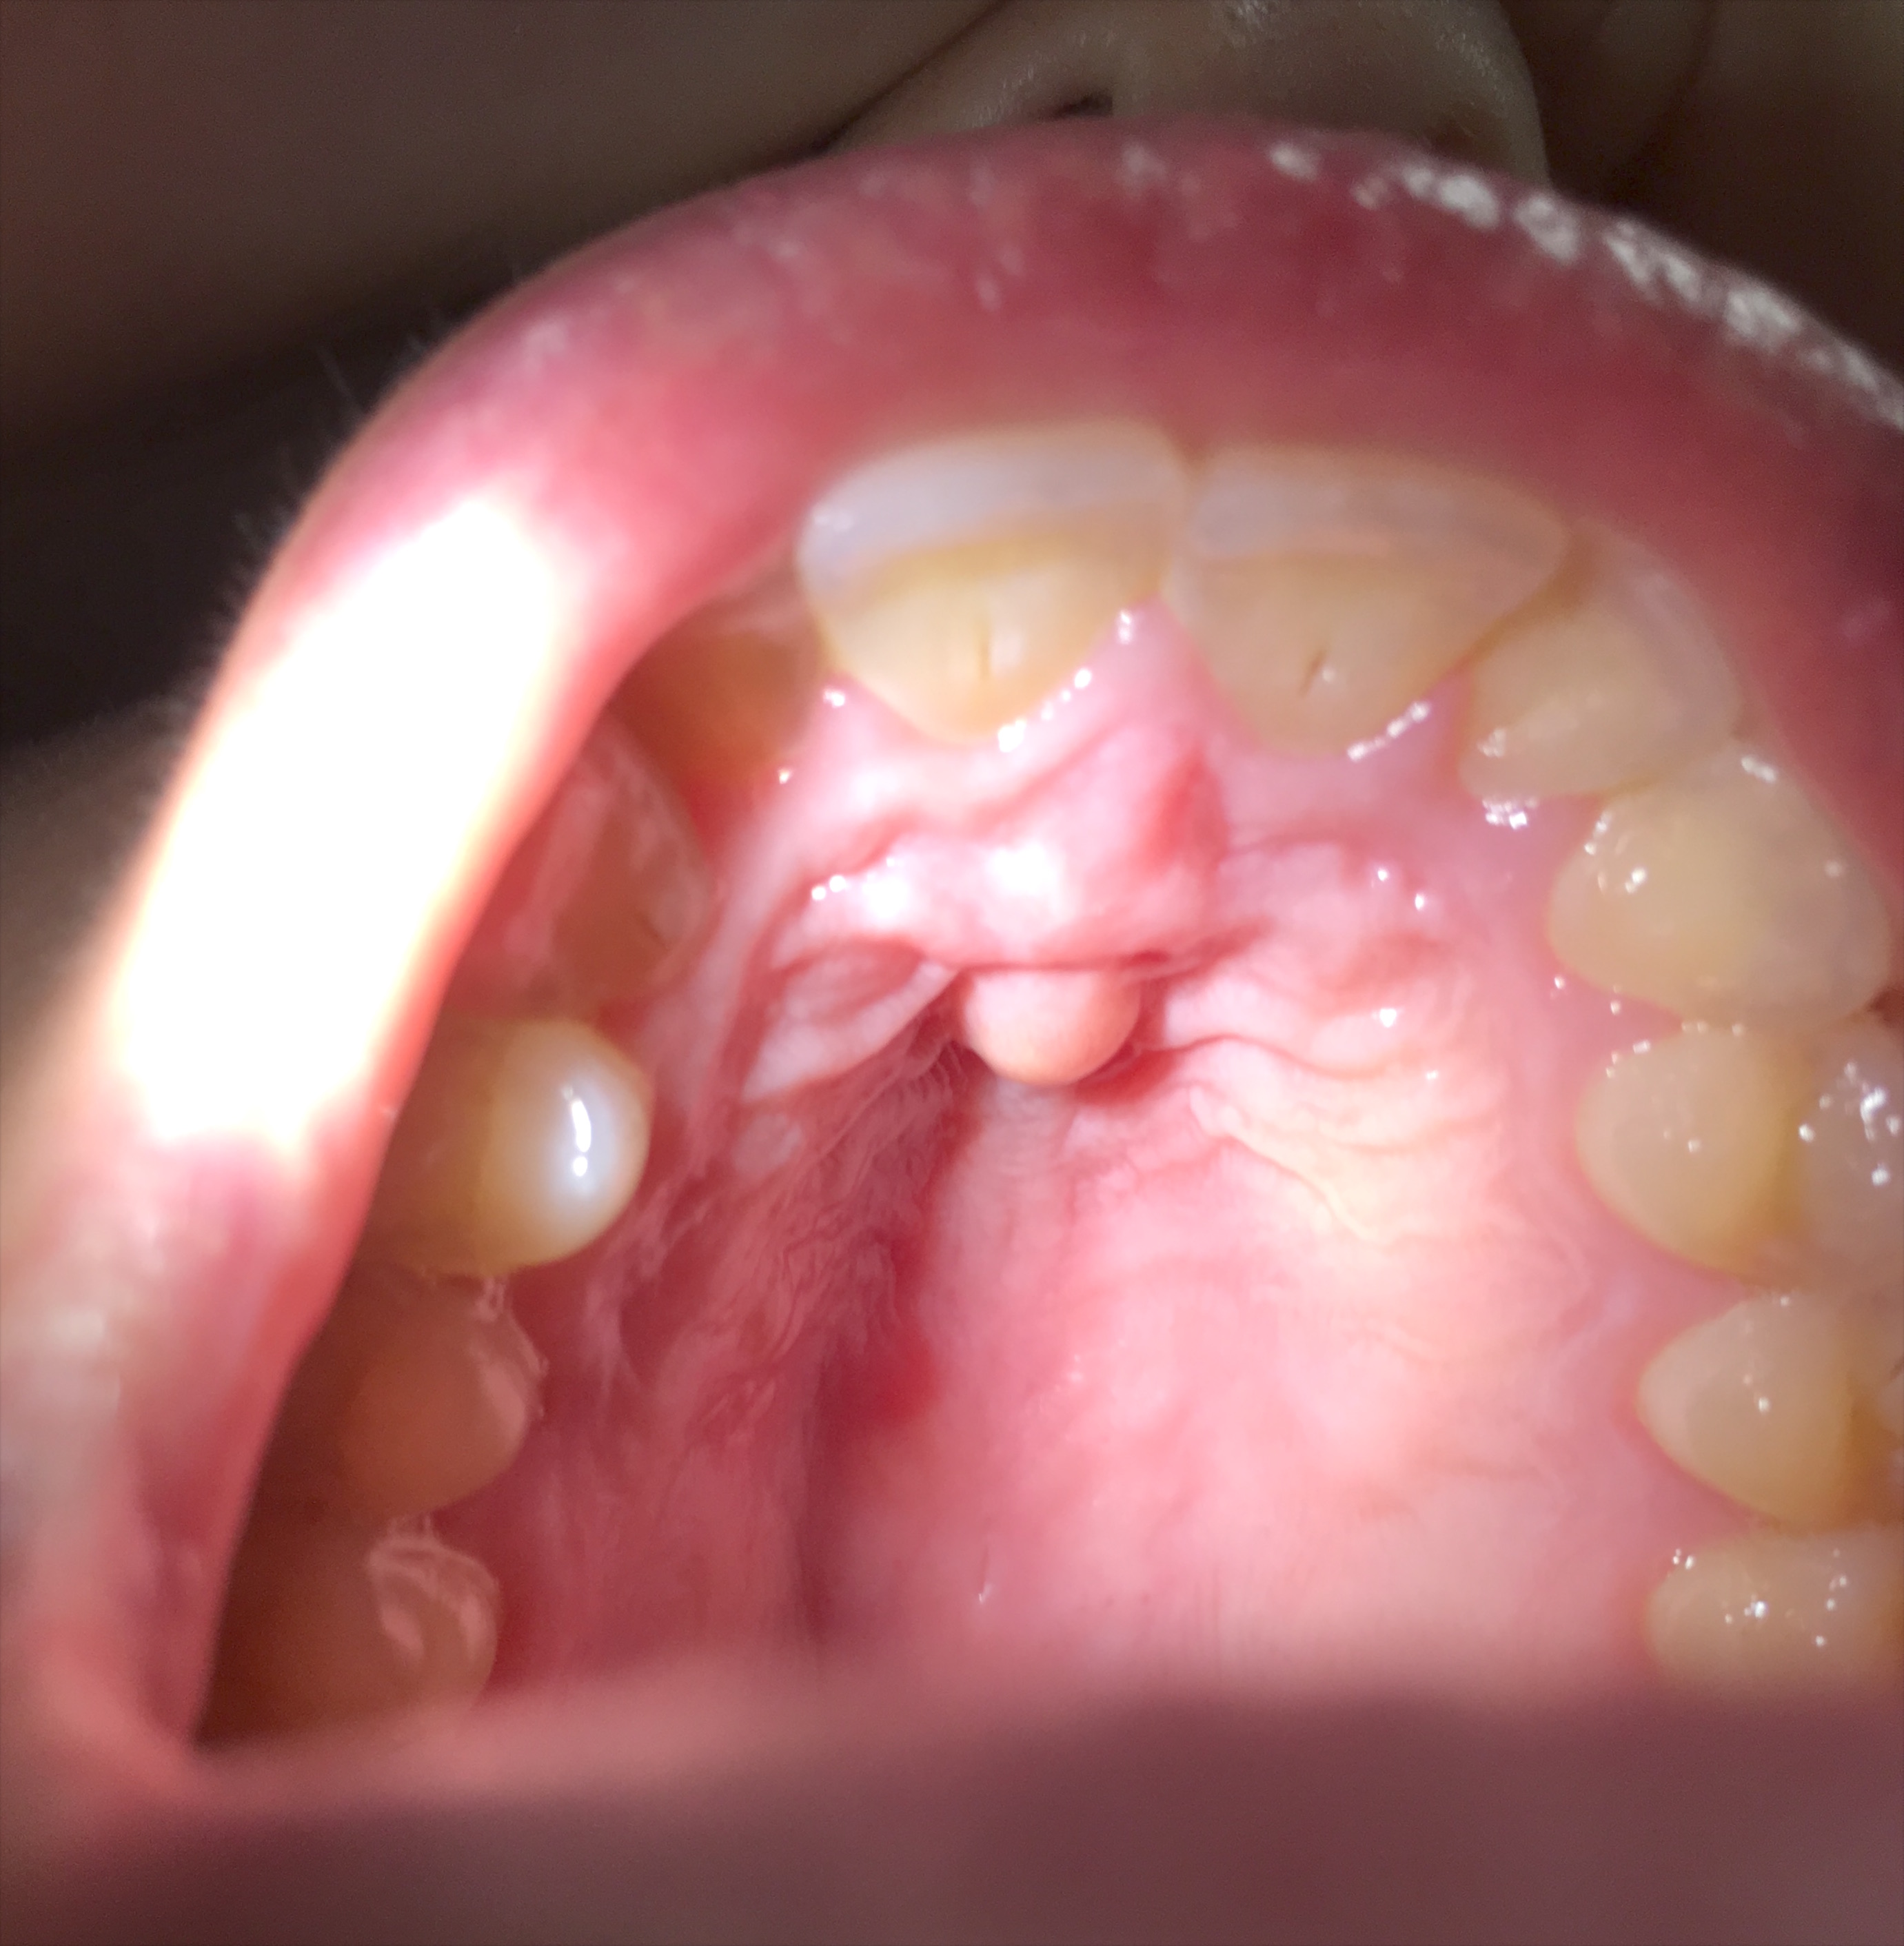

A cursory ENT exam shows all to be normal. He does have some fullness and percussion tenderness over the left maxillary sinus. But there is a definite lump on the palate:

The lump is firm, tender but not particularly hot. It is bang in the midline: